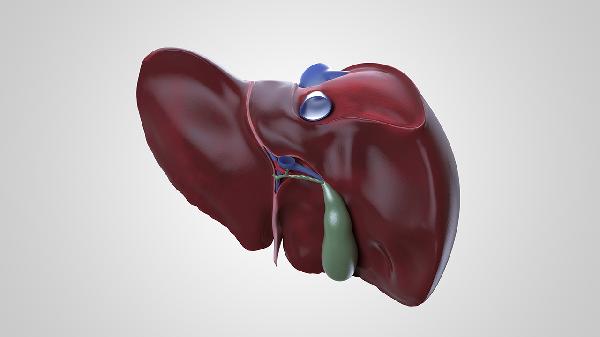

检查肝脏通常需要进行肝功能检查、肝脏超声检查、肝脏CT检查、肝脏MRI检查以及肝脏弹性检查等。肝脏检查有助于评估肝脏健康状况,及时发现肝脏疾病。

肝脏超声检查是利用超声波对肝脏进行成像的无创检查方法。通过超声检查可以观察肝脏的大小、形态、边缘、内部回声等特征,发现肝脏占位性病变、脂肪肝、肝硬化等异常改变。超声检查具有操作简便、无辐射、可重复进行等优点,是肝脏疾病筛查和随访的重要检查手段。对于可疑肝脏病变,超声检查常作为首选影像学检查方法。